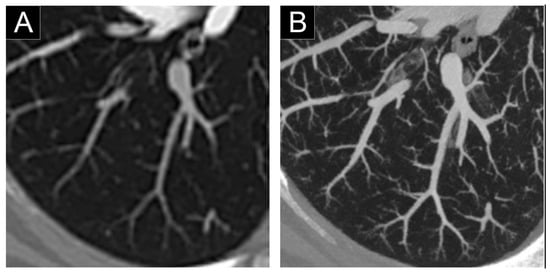

3.7. Pulmonary Vascularization Imaging

- Si-Mohamed, S.; Boccalini, S.; Rodesch, P.-A.; Dessouky, R.; Lahoud, E.; Broussaud, T.; Sigovan, M.; Gamondes, D.; Coulon, P.; Yagil, Y.; et al. Feasibility of lung imaging with a large field-of-view spectral photon-counting CT system. Diagn. Interv. Imaging 2021, 102, 305–312. [Google Scholar] [CrossRef] [PubMed]

- Bartlett, D.J.; Koo, C.W.; Bartholmai, B.J.; Rajendran, K.; Weaver, J.M.; Halaweish, A.F.; Leng, S.; McCollough, C.H.; Fletcher, J.G. High-Resolution Chest Computed Tomography Imaging of the Lungs: Impact of 1024 matrix reconstruction and photon-counting detector computed tomography. Investig. Radiol. 2019, 54, 129–137. [Google Scholar] [CrossRef]